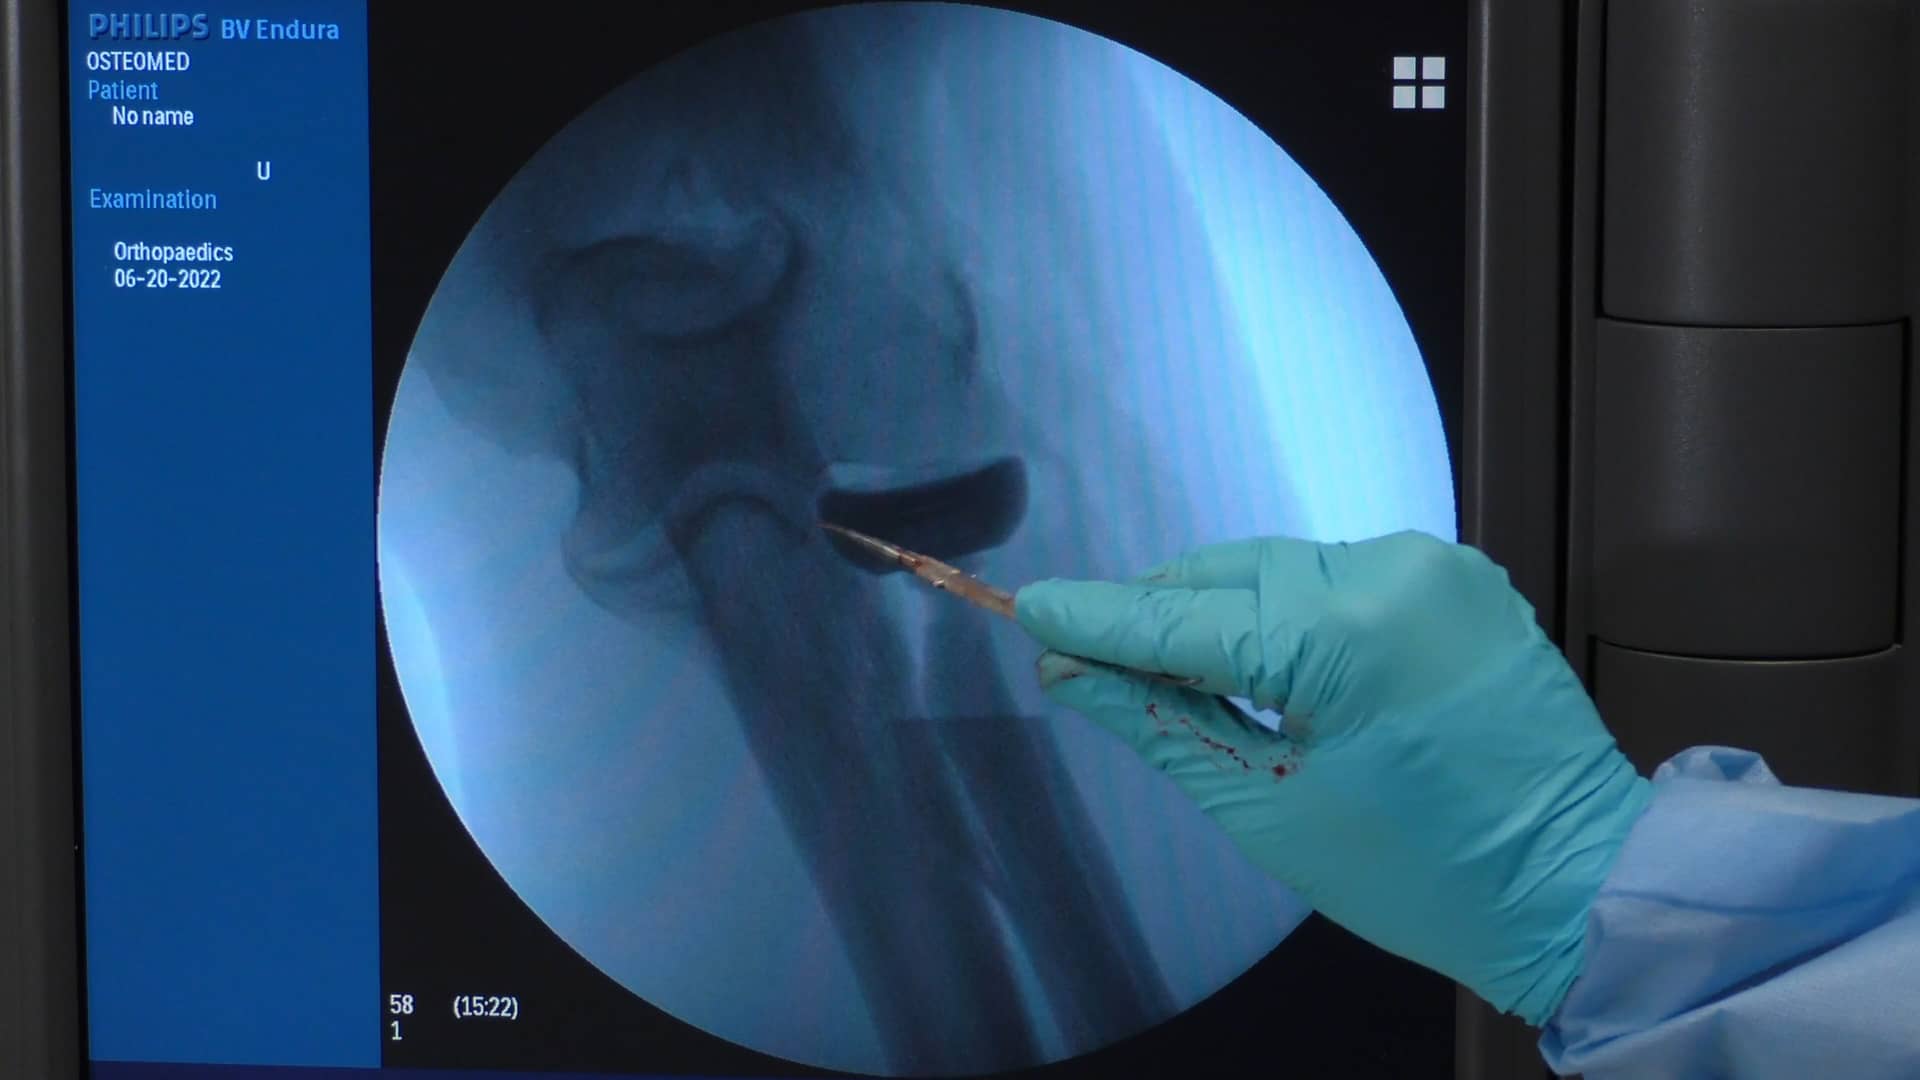

From www.osteomedcorp.com

Anatomic Radial Head Solutions 2 Acumed Why Is Radial Stem Placement An Important Mechanic Radial head prostheses can be implanted using different fixation approaches, and cemented stems are broadly described. Radial head fractures are often secondary to a direct axial force, such as that involved in motor vehicle accidents and falls on an outstretched. L2l radial head system is the simple solution for replacing the proximal radial head in patients with fractures. It was. Why Is Radial Stem Placement An Important Mechanic.